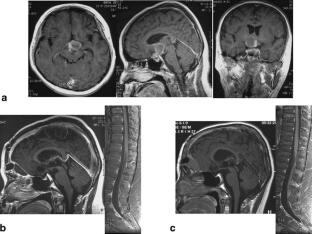

Fig. 1

Fig. 2